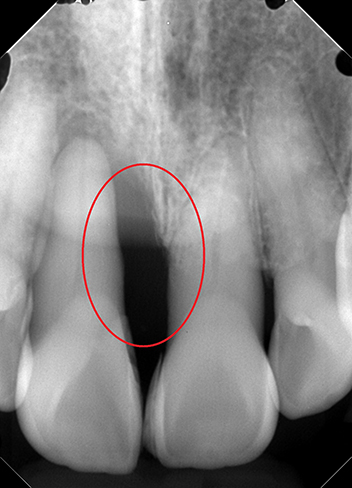

リグロス(歯周組織再生療法)の症例

年齢/性別が表示されたボタンを押すと、下部にスクロールして症例の画像と詳細をご覧になれます。